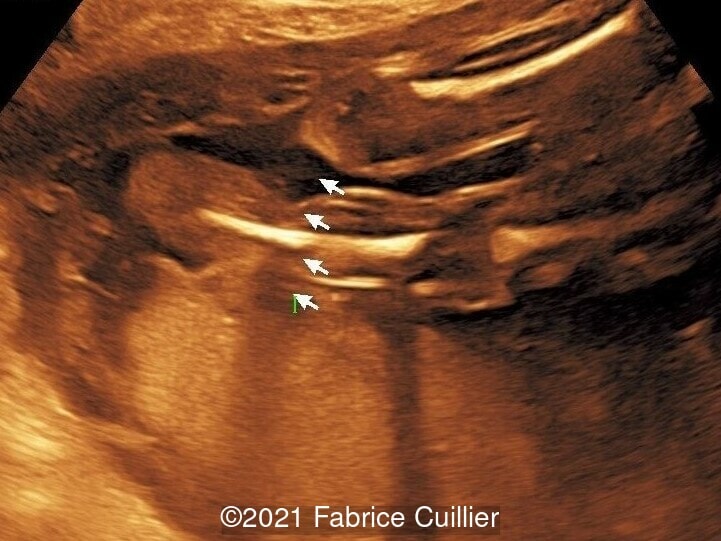

• Images 2-4: Ultrasound at 22 weeks gestation showing left foot edema with narrowing and stricture of the soft tissue due to an amniotic band (marked as ? on image 2).

• Images 5-7, video 1: Ultrasound at 23 weeks gestation showing similar finding to images 2-4.